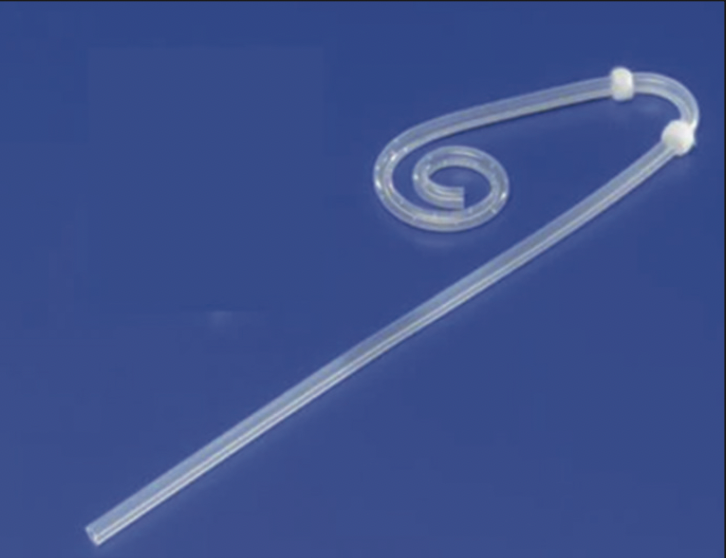

Tomás González Arestizábal, Constanza Dictter, Paulina Abara, Vicente Villegas, Catalina Torres, Antonella Sanguineti

|

|

|